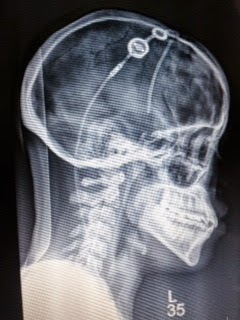

Doesn’t sound like it’s working to me. I had explained to my doctor my suspicions of the shunt not draining properly based on what I’ve read online. Since it was in the wrong way for four year, it could have extra cerebral spinal fluid that wasn’t reabsorbed properly. It’s just my opinion and I surprised no one else has thought of this yet. Technology just isn’t there as far as I’m concerned. I had told him numerous times before I had the revision/brain injuries in March I needed a full shunt revision which means changing out the entire system. He didn’t listen to me. I took a huge risk learning how to walk again with the catheter broken in my stomach for an extra two months. I had complained about having stomach and abdominal pains for months before it was fixed.

We need to have shunts that at least have the following:

1. Shunts that have expiration dates so you and your doctor know how much time you have left before it expires.

2. Shunts which give off an indication whether it’s a light on your arm, head or something telling you it’s about to malfunction.

3. Technology advanced like it is was in Star Trek where once you’re scanned with the laser gun you have a reading on the computer of what’s broken and needs to be fixed.